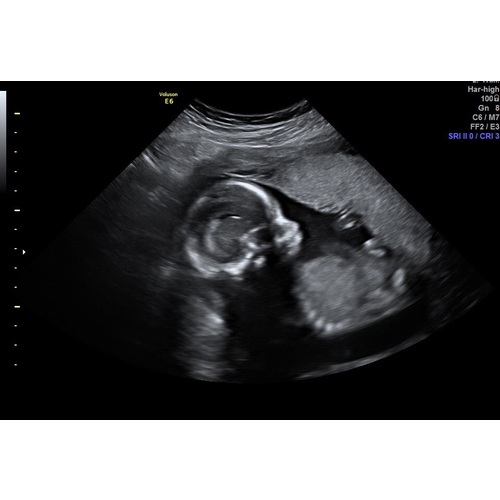

Jullie hebben de lengte en gewicht te horen gekregen van jullie kindje? Ik niet, sowieso was het super gehaast (door Corona houden ze alles zo kort mogelijk, bizar genoeg)

Ik heb al 3 kinderen bij de 12 en 20 weken echo en een nog iets latere exact weet ik het niet ... kreeg ik ook nog een echo met cijfertjes en wat woorden waar ik den helft niks van begrijp 🙊

Maar de lengte en het gewicht staan er wel op . Heb je zoiets gekregen ?